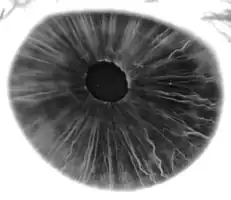

The iris (pl.: irides or irises) is a thin, annular structure in the eye in most mammals and birds that is responsible for controlling the diameter and size of the pupil, and thus the amount of light reaching the retina. In optical terms, the pupil is the eye's aperture, while the iris is the diaphragm. Eye color is defined by the iris.

The iris consists of two layers: the front pigmented fibrovascular layer known as a stroma and, behind the stroma, pigmented epithelial cells.

The stroma is connected to a sphincter muscle (sphincter pupillae), which contracts the pupil in a circular motion, and a set of dilator muscles (dilator pupillae), which pull the iris radially to enlarge the pupil, pulling it in folds.

The back surface is covered by a heavily pigmented epithelial layer that is two cells thick (the iris pigment epithelium), but the front surface has no epithelium. This anterior surface projects as the dilator muscles. The high pigment content blocks light from passing through the iris to the retina, restricting it to the pupil.[3] The outer edge of the iris, known as the root, is attached to the sclera and the anterior ciliary body. The iris and ciliary body together are known as the anterior uvea. Just in front of the root of the iris is the region referred to as the trabecular meshwork, through which the aqueous humour constantly drains out of the eye, with the result that diseases of the iris often have important effects on intraocular pressure and indirectly on vision. The iris along with the anterior ciliary body provide a secondary pathway for aqueous humour to drain from the eye.

The iris is divided into two major regions:

1. The pupillary zone is the inner region whose edge forms the boundary of the pupil.

2. The ciliary zone is the rest of the iris that extends to its origin at the ciliary body.

The collarette is the thickest region of the iris, separating the pupillary portion from the ciliary portion. The collarette is a vestige of the coating of the embryonic pupil.[3] It is typically defined as the region where the sphincter muscle and dilator muscle overlap. Radial ridges extend from the periphery to the pupillary zone, to supply the iris with blood vessels. The root of the iris is the thinnest and most peripheral.[4]